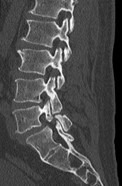

治療について

受診された際には問診、診察を行い、画像検査(レントゲン、MRI、CT)や採血検査を行い、診断を付け、治療方針を説明します。 上記のような保存治療を行っても取れない痛みや、手の使いにくさや歩行困難、排尿排便障害などが出現し症状が進行性の場合は手術加療が必要となります。

手術・検査

なるべく低侵襲で体の負担が少ない手術を行います。低侵襲な脊椎手術には、手術による傷が小さい、筋肉の損傷が少ない、出血量が少ない、時間が短い、術後の痛みが少ない、早期リハビリテーションが可能、早期退院が可能(10日程度)、早期社会復帰が可能、など多くの利点が挙げられます。

検査

当院では、術前の診断精度を高める目的で、神経根ブロック(左)やCTミエログラフィー(右)検査を行っています。検査後は、経過を確認する目的で1泊入院となりますが、翌日には退院が可能です。